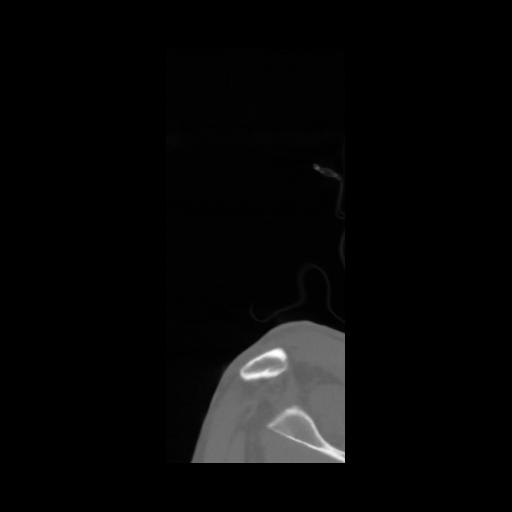

14 P.BLANDAS,,Sagittal,2.000,P.BLANDAS,Sagittal,